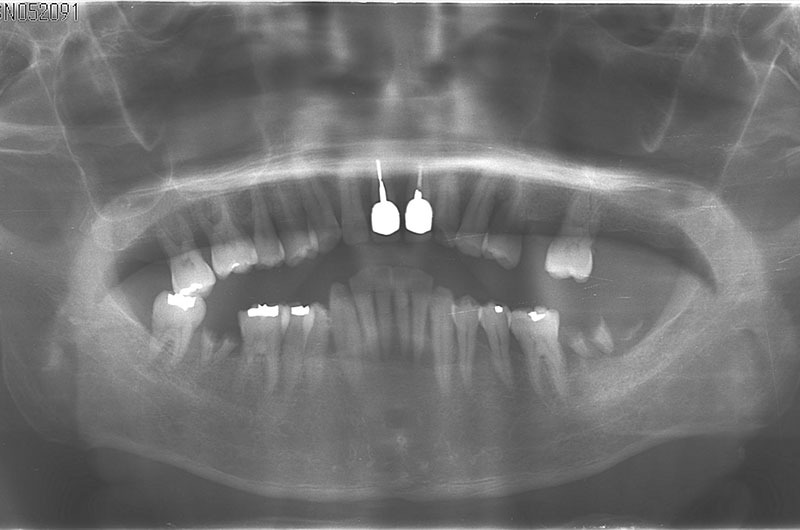

インプラント治療 ①

before

after

• 年齢

59歳

• 性別

男性

• 治療期間

8ヵ月

• 費用

887,250円